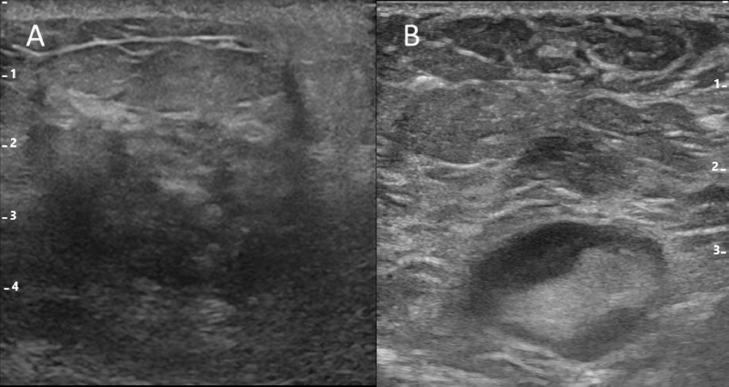

A useful case of ultrasound-guided axillary lymph node aspiration in a breast cancer patient with improved needle visibility.

Ultrasound-guided, lymph node, fine-needle aspiration cytology is important in diagnosing axillary lymph node metastasis in breast cancer. However, poor needle visibility can render the procedure difficult. We describe a case in which state-of-the-art enhancement techniques using matrix linear probes can provide better needle visibility and improve the certainty and efficiency of the examination.